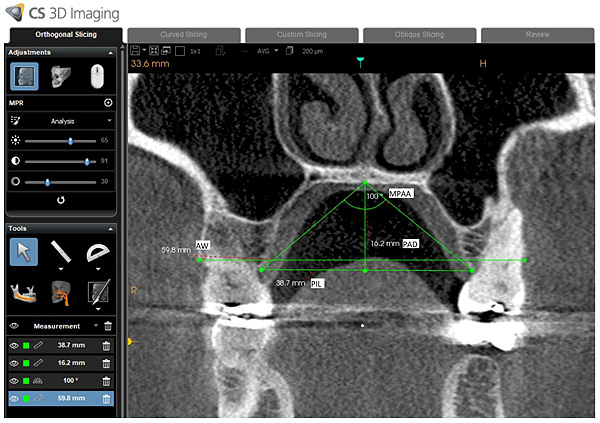

For hard palate measurements (Fig. 3), the following measurements were obtained following the examples of Akbay and Lim et al. [27, 28]:

(1) Palatal Interalveolar Length (PIL): Top-view length of the line from one side' alveolar crest to the same point of the other side’s alveolar arch.

(2) Palatal Arch Depth (PAD): The length of the line from the intersection of hard palates to the inter-alveolar line.

(3) Maxillopalatal Arch Angle (MPAA): The angle which is formed by the lines from the interpalatal’s mergence point to both crests of alveolar arches.

(4) Palatal arch depth/palatal inter-alveolar length (PAD/PIL): The ratio of hard palate depth to the inter-alveolar length.

(5) Alveolar Width (AW): The distance between right and left buccal alveolar bone

All of the hard palate measurements were obtained on a coronal section at mid-point of the hard palate length. The mid-point is the point located in the middle of the distance between anterior nasal supine and posterior nasal supine in the mid-sagittal plane (Fig. 4).